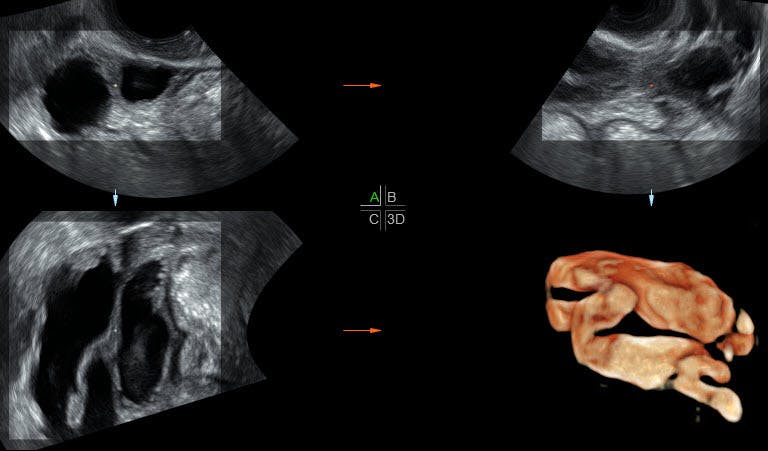

Biopsy which involves taking small tissue samples from the uterus. Pelvic sonography is performed commonly in patients who have a clinical diagnosis of pelvic inflammatory disease. Historically PID has been a clinical diagnosis supplemented with the findings from ultrasonography US or magnetic resonance MR imaging. A right adnexal dead end tubular fluid filled structure with typical mucosal infoldings toward the lumen thick wall and a debris-fluid level ultrasound image characteristic of a dilated fallopian tube in this case. Biopsy which involves taking small tissue samples from the uterus. A connected ultrasound system is another very helpful feature for the PID patient. Ultrasound findings of Pelvic Inflammatory Disease PID. Though PID is clinically diagnosed ultrasound imaging is the first-line radiologic evaluation method of choice for PID and may be used to appreciate the following. 20 21-year-old woman with pelvic inflammatory disease.